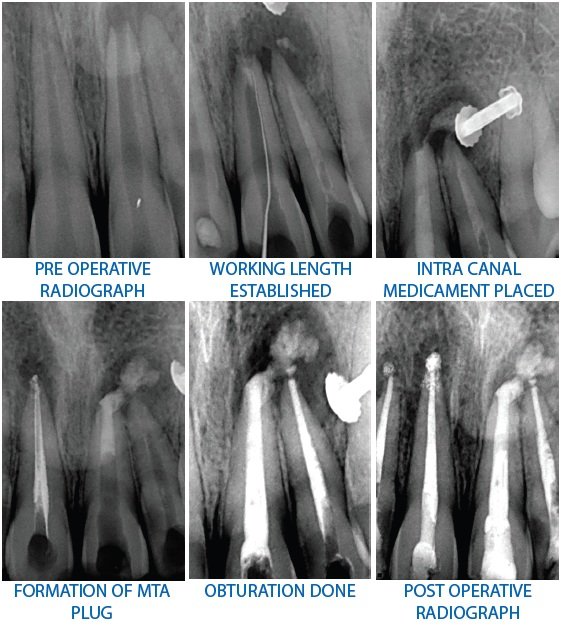

How to Endodontics The State of the Art PDF) Special Issue “The State of the Art in Endodontics”の詳細情報

PDF) Special Issue “The State of the Art in Endodontics”。APEXIFICATION USING MTA- A CASE SERIES。State of the art and science of endodontics - ScienceDirect。

商品説明

「HowtoEndodonticsTheStateoftheArt」